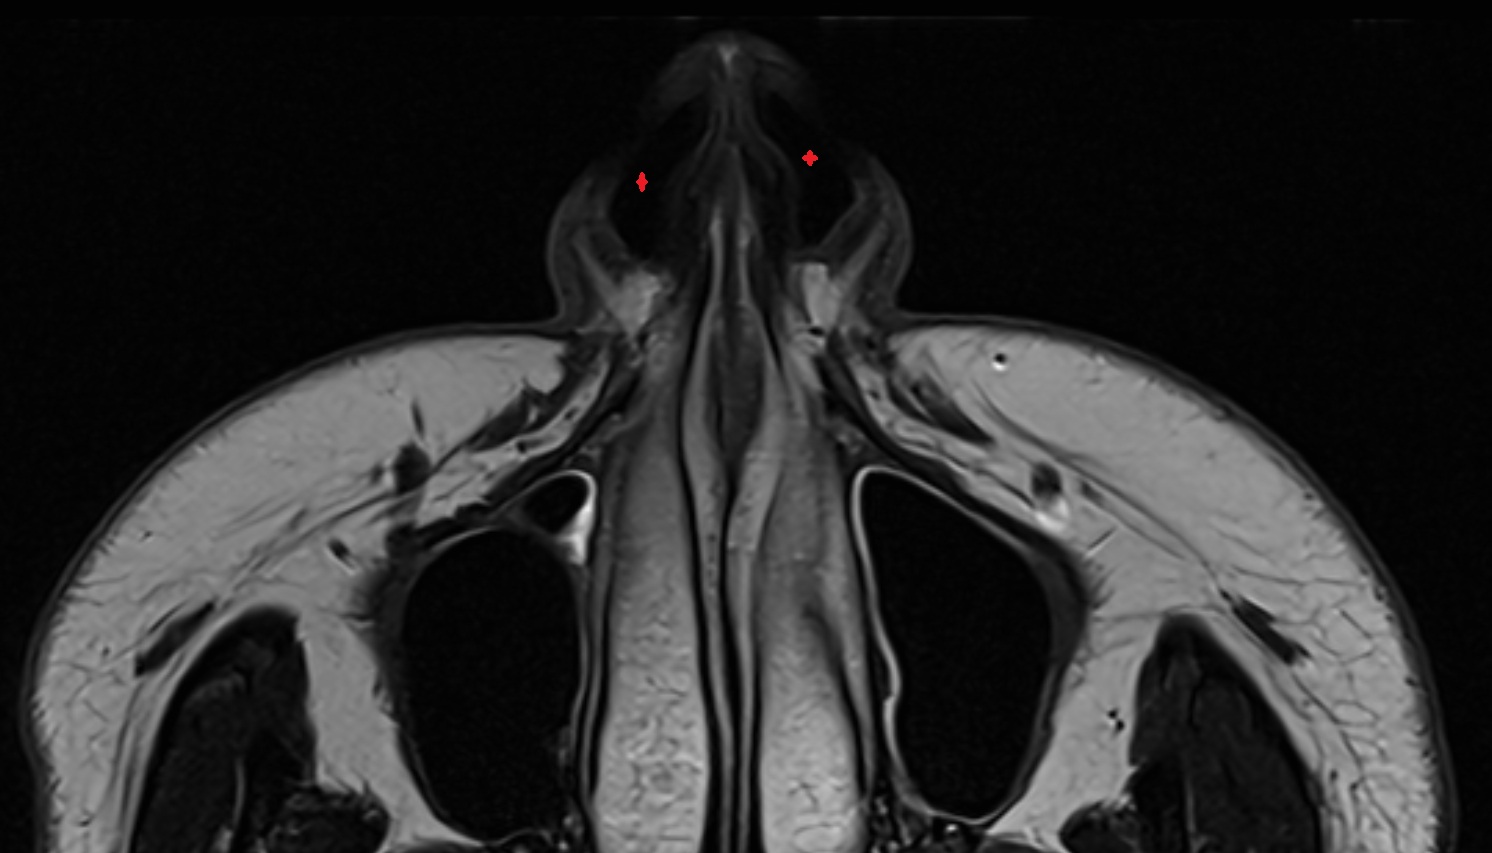

- Nasolacrimal duct (Tear duct)